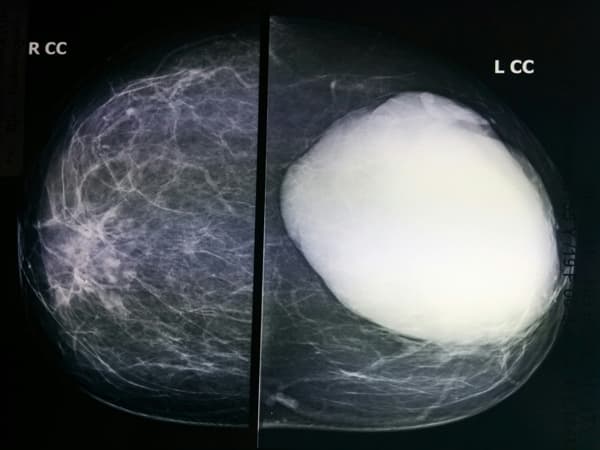

U diệp thể vú là gì?

Các triệu chứng của U diệp thể

U diệp thể là khối u hiếm ở vú, chỉ chiếm 1% trong tổng số các khối u ở vú. U diệp thể theo tiếng Hy Lạp có nghĩa là giống hình lá, đề cập đến việc các tế bào khối u phát triển trong một mô hình giống như chiếc lá. Các triệu chứng […]

Điều trị u diệp thể

U diệp thể là khối u hiếm ở vú, chỉ chiếm 1% trong tổng số các khối u ở vú. U diệp thể có thể là u lành tính hoặc ác tính, tuy nhiên cách điều trị u diệp thể là tương đương nhau, thường bao gồm phẫu thuật loại bỏ khối u và vùng […]